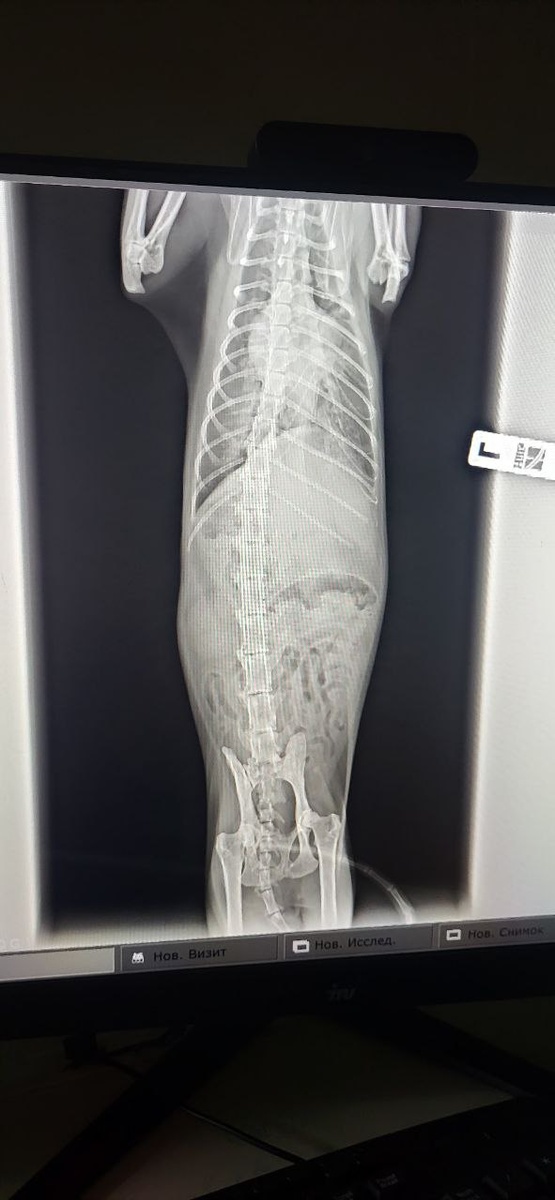

Не знаю, что тут с легкими, жду результаи и едем к З

П. она пусть рассмотрит этот рентген, есть тут опухоль или только выпот Он сегодня опять начал тяжело дышать: 80 движений в минуту при норме 30, и я сделала преднизолон и круто изменила планы на день: вот поехали по барам ветклиникам)) Надеюсь, все не зря. 9 лет назад я его и брата Леву вытащила из состояния скорее мертв чем жив. Сейчас я тоже верю, что получится! Спасибо! Большое спасибо за помощь!